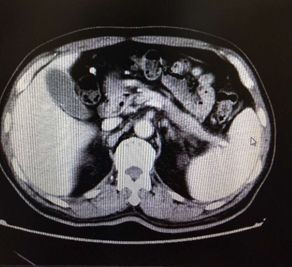

腹部CT检查结果如下:

考虑慢性胰腺炎,脾静脉血栓形成,伴脾门及胃周多发侧枝血管形成,同时合并腹主动脉夹层ⅢB型(Debakey分型),立即严格控制血压在120/80 mmHg一下,同时内科止血、输血后HGB达97 g/L转外科进一步治疗(脾切除术+胃周血管离断术以及腹主动脉支架植入术)。

本例是慢性胰腺炎所致胰源性门脉血栓引起的胰源性门脉高压症同时合并腹主动脉夹层ⅢB型(Debakey分型)。